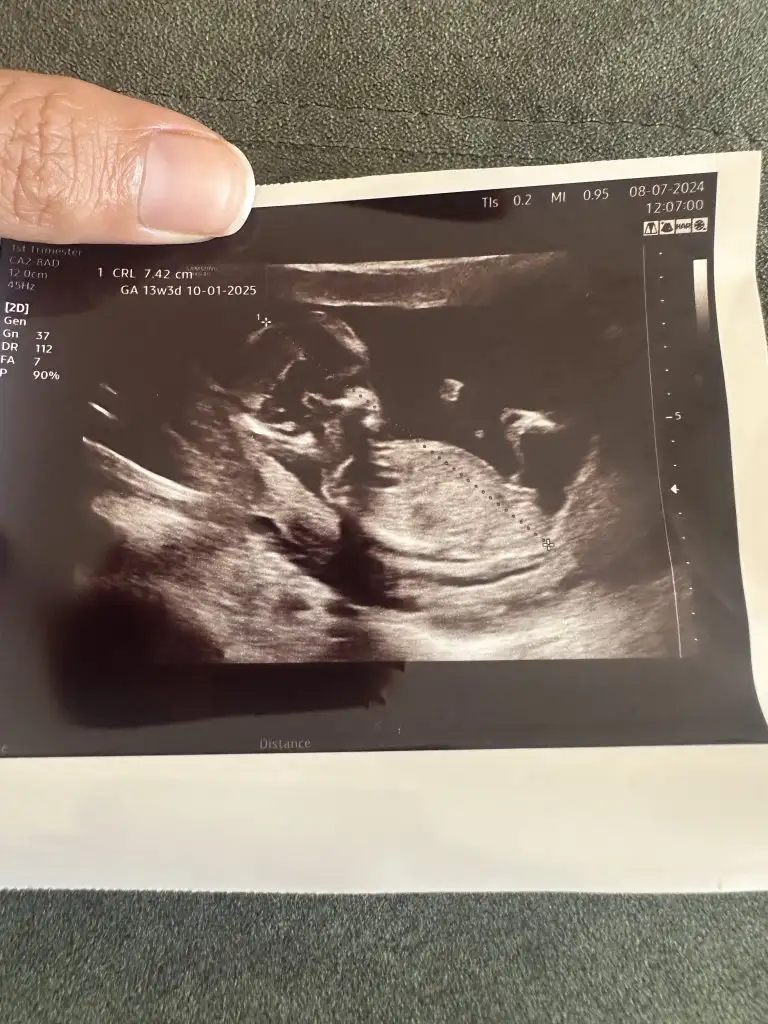

Canim 13 haftalik bakarmisiniz

Eklentiler

• IMG_5070.webp

27,2 KB · Görüntüleme: 35